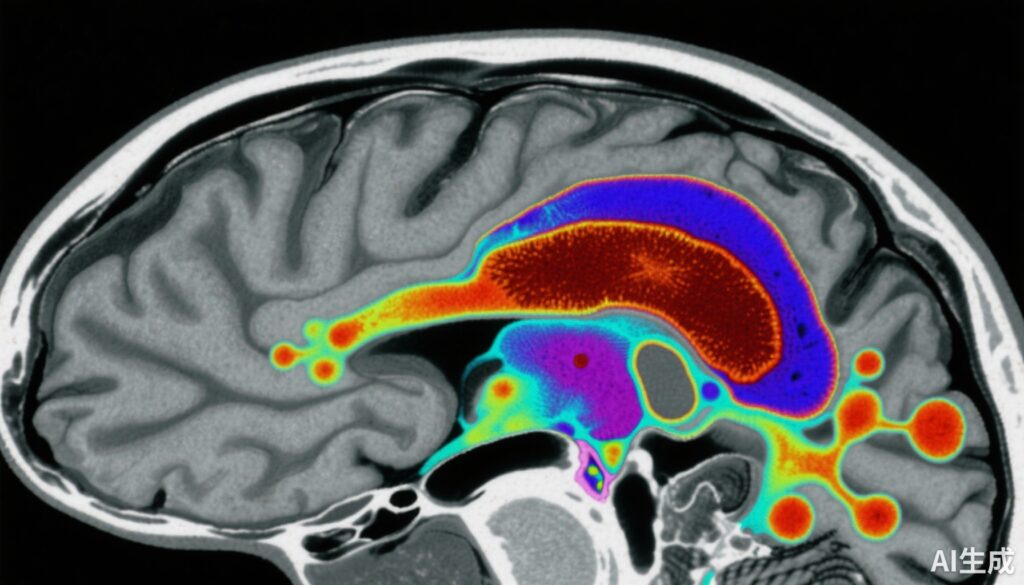

この症例対照研究には159人の参加者が含まれました:80人の健常対照群と79人の早期統合失調症患者(抗精神病薬未使用または抗精神病薬非摂取患者を含む)。黒質-腹側被蓋野(SN-VTA)の磁気感受性は、組織鉄レベルの非侵襲的マーカーを提供する定量的磁気感受性マッピング(QSM)MRIによって測定されました。

最後に、統合失調症患者40人で、[18F]-DOPA正電子断層撮影(PET)により尾状核の多巴胺合成能力が測定され、SN-VTAの鉄含有量とドーパミネルギック活性との相関分析が可能になりました。

1. 統合失調症におけるSN-VTA磁気感受性の低下:患者は対照群と比較してSN-VTAでのQSM値が有意に低く(効果サイズd = -0.66、95%CI -0.98から-0.34)でした。これは、この重要なドーパミネルギック領域での脳内鉄レベルの低下を示しています。

3. SN-VTA鉄と尾状核多巴胺合成能力の逆相関:統合失調症患者では、SN-VTAの磁気感受性の低下が、尾状核多巴胺合成(Ki cer)の増加と有意に関連していた(相関係数r = -0.44)。神経メラニンとミエリンの測定値を制御した後も、この関係性は有意でした。

4. 地域特異性:最も顕著な効果は、尾状核ドーパミネルギックトーンを調節する役割を持つSN-VTAの腹側部分に局在していました。